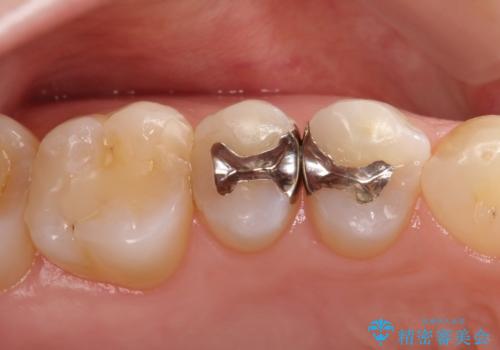

- 金属の詰め物を外して、セラミックインレーを入れたいと来院された患者様です。

奥歯に虫歯も認め、3歯の治療を来院回数2回で終了で終了しています。